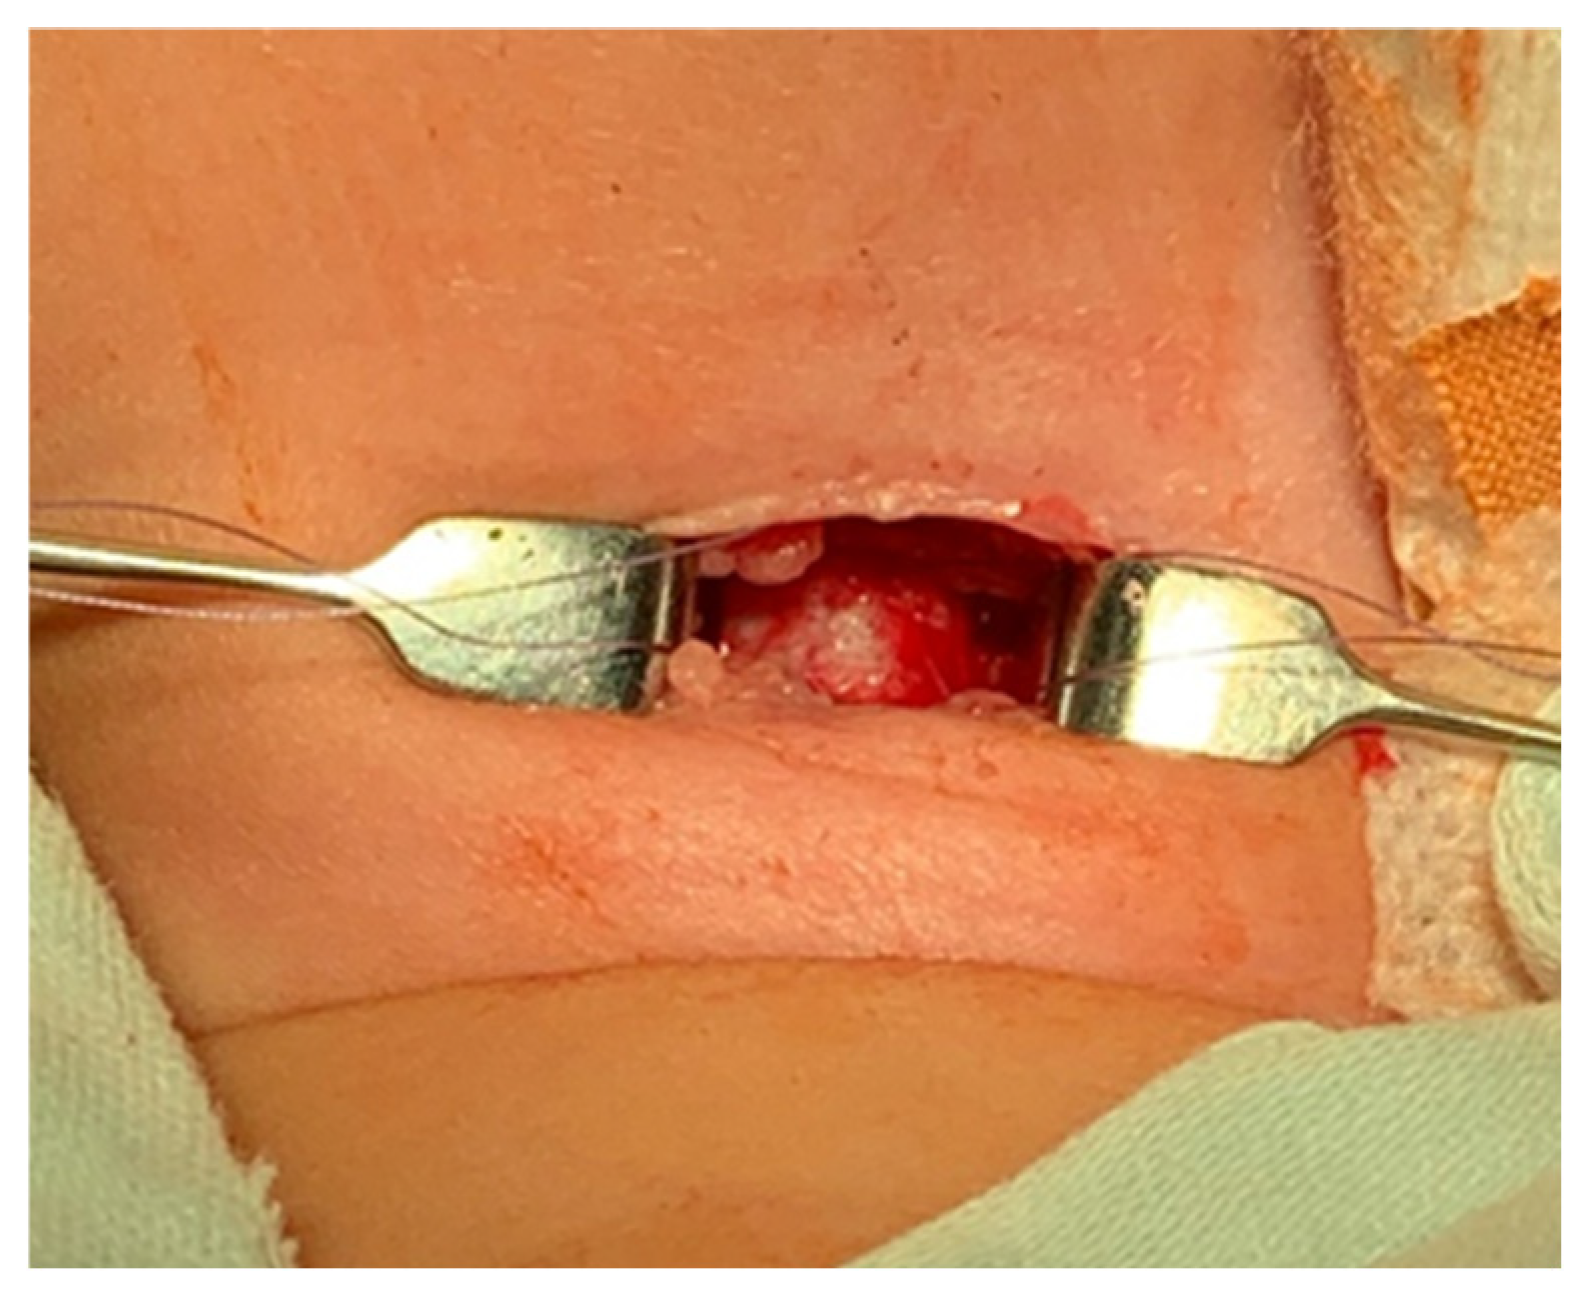

- The platysma is reached, and its muscles are separated and retracted using retractors (Figure 3).

- Bipolar cautery is used during the procedure for hemostasis (Figure 4).

- The pretracheal longitudinal muscles are exposed, separated along the midline of the neck, and retracted laterally.